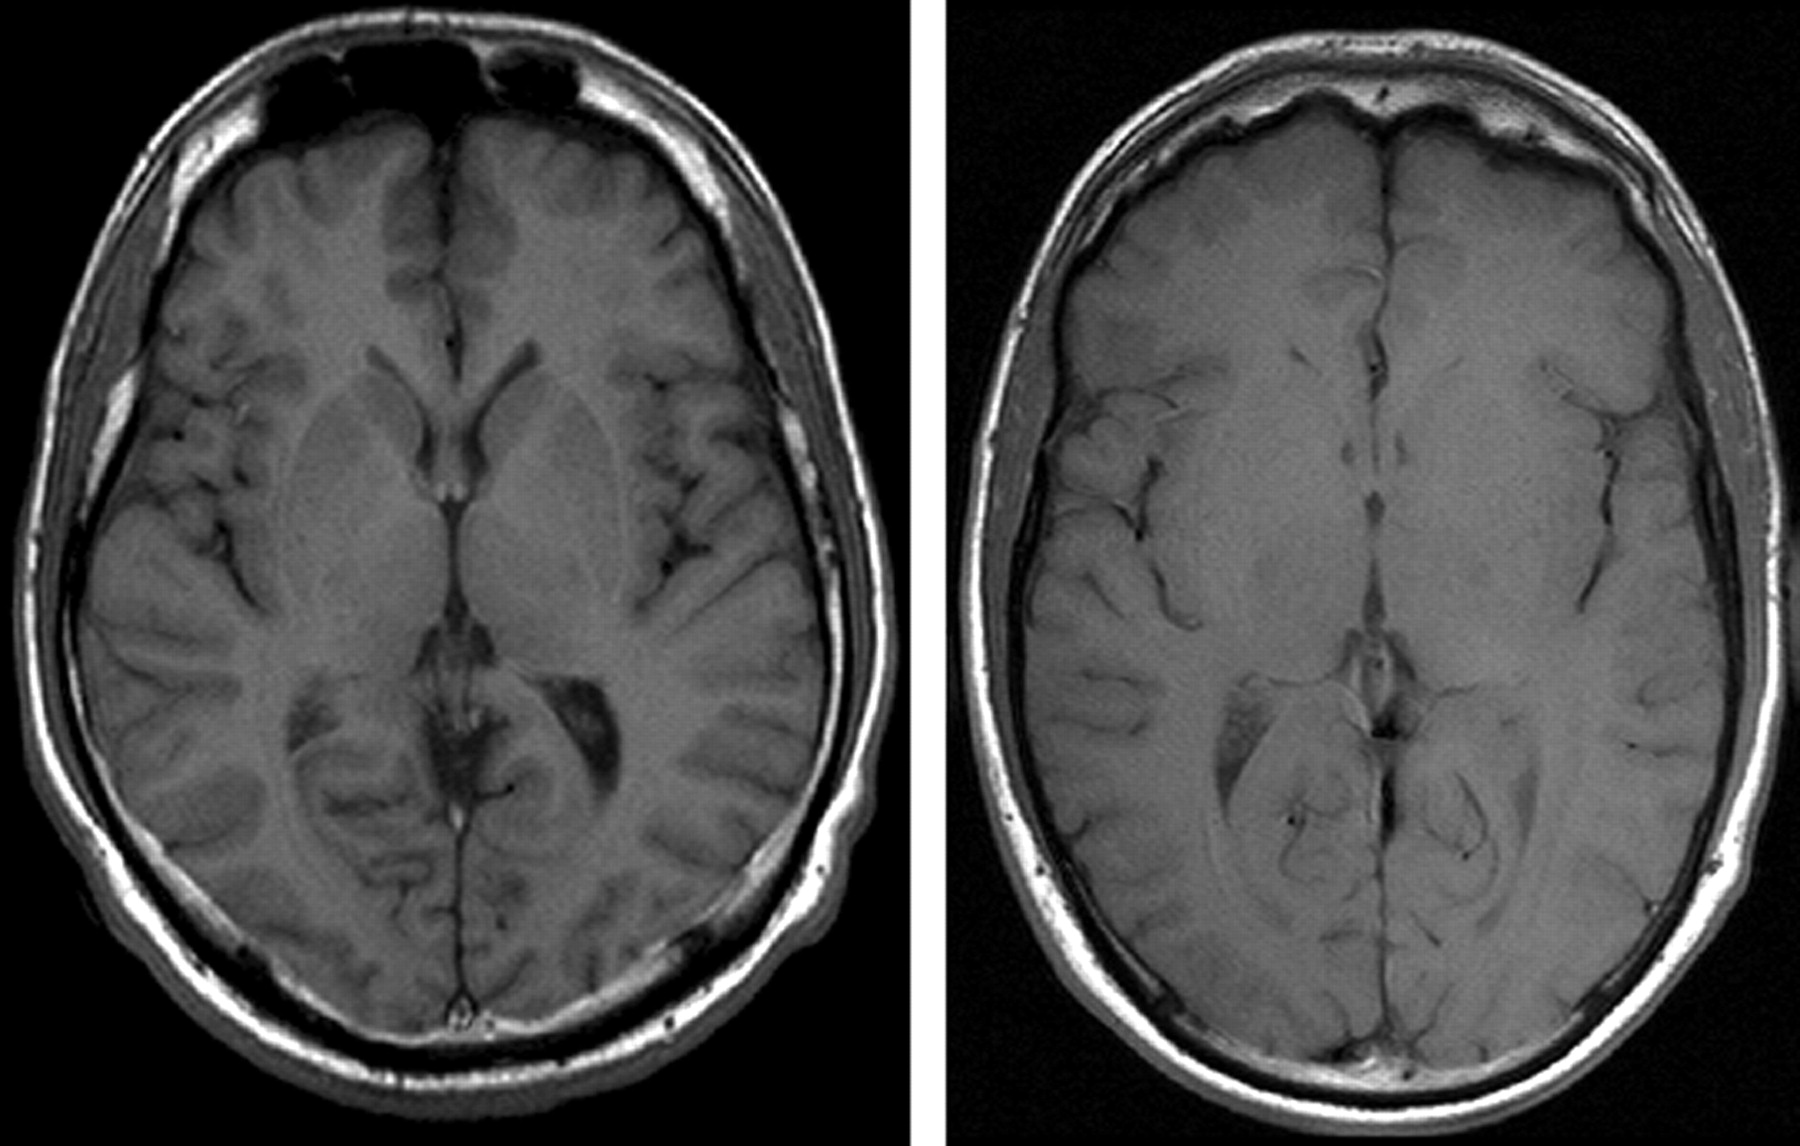

The use of gradient echo sequences is a valuable alternative (Fig 5) to the approach discussed above to significantly reduce SAR. These sequences, however, are prone to susceptibility artifacts especially at higher B0 and longer TE, limiting their use at 3T.

Gradient echo T1 (left: TR, 311 ms; TE, 2.5 ms; section thickness, 5 mm; matrix, 512 × 256; FOV, 220 × 220 mm2; bandwidth, 465 Hz/pixel; flip angle, 90°) compared with T1 spin-echo (right: TR, 700 ms; TE, 10 ms; section thickness, 5 mm; matrix, 256 × 192; FOV, 220 × 220 mm2; bandwidth, 200 Hz/pixel; flip angle, 90°) in the same subject at 3T, which indicates higher contrast in gradient echo than spin-echo sequences at 3T.